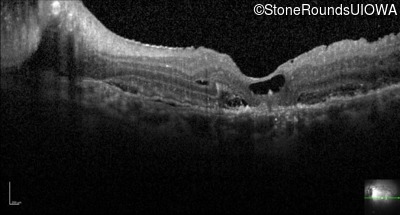

Optical Coherence Tomography - Right - 20/50 -3

Exemplar / OCT Stack

Optical Coherence Tomography - Left - Count Fingers 6"